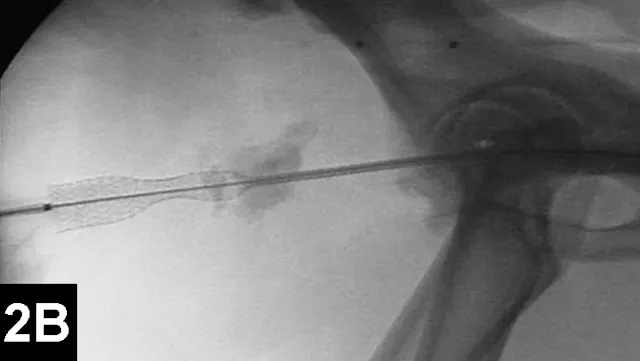

IR techniques that involve placement of an intraluminal stent to alleviate signs associated with malignant obstructions have been described in veterinary patients (Figure 2).5 The author has performed multiple palliative stenting procedures in the urinary tract and upper and lower GI tracts and has relieved luminal obstructions caused by neoplasia or intractable benign strictures in many different sizes of animals, including ferrets.5-11 The IR techniques were fast, safe, and effective. Complications were minor and uncommon.

Figure 2A: Serial lateral positive contrast urethrocystograms in a dog with a malignant urethral obstruction secondary to a prostatic tumor.

Maximal urethral diameters measured using a colonic marker catheter to adjust for radiographic magnification.